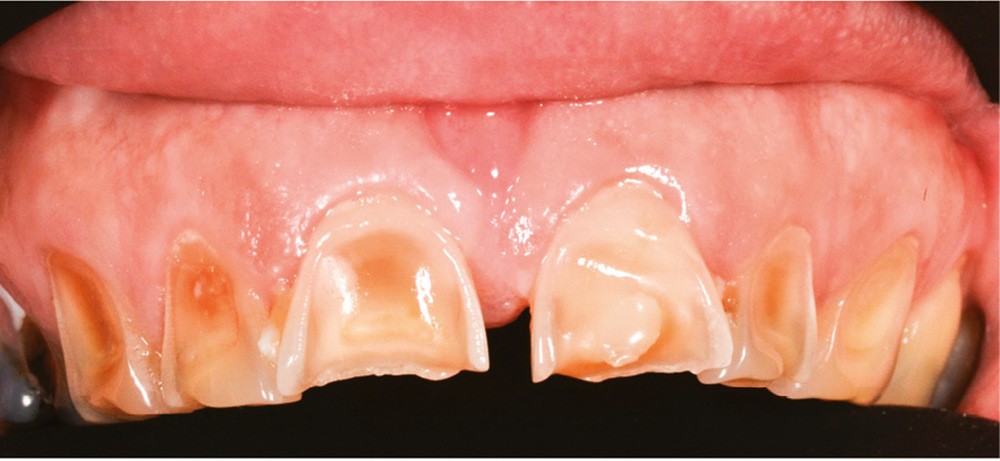

Les modifications hormonales à mettre en relation avec l’hygiène bucco-dentaire, les paramètres socio-économiques, l’âge précoce de la grossesse ainsi que l’augmentation du grignotage pourraient augmenter la prévalence des caries dentaires chez la femme enceinte. Ces patientes sont régulièrement sujettes à des envies multipliant le nombre de prises alimentaires souvent très riches en sucre. Ces apports sucrés, associés à la baisse du pH salivaire lors de la grossesse, entraînent un déséquilibre du cycle déminéralisation et de reminéralisation. Le risque carieux peut être augmenté, ainsi que la susceptibilité à l’érosion dentaire accrue par les vomissements et/ou les reflux gastro-œsophagiens [2]. L’action hormonale peut également avoir des répercussions sur les tissus parodontaux. La gingivite gravidique observée sur plus d’une femme enceinte sur deux, constitue une réponse inflammatoire de la gencive exacerbée par la présence de plaque bactérienne, et favorisée par l’augmentation des taux d’œstrogène et de progestérone [3] (fig. 1). 5 % des futures mères développeront un épulis, dont l’étiologie reste méconnue (fig. 2) [4].

Le processus d’érosion peut être divisé en deux étapes. La première est une déminéralisation partielle. À ce stade, une reminéralisation reste possible car de l’émail déminéralisé subsiste et des ions, calciums, phosphates ou du fluor, peuvent encore s’y fixer. Quand l’utilisation d’un acide devient trop fréquente par rapport aux processus de reminéralisation, les couches superficielles d’émail fragilisées à l’occasion de la première étape sont éliminées. La perte de substance est alors irréversible (fig. 5). Après la perte de l’émail, celle de la dentine sera plus rapide du fait de sa moindre minéralisation [12]. Ces lésions peuvent entraîner des sensibilités difficiles à éradiquer et créer un déficit esthétique, à l’opposé de l’effet recherché initialement. Les effets déminéralisants de l’acide citrique, rendraient la dent plus sensible aux lésions d’abrasion et d’attrition, augmentant d’autant plus la perte de substance [14].